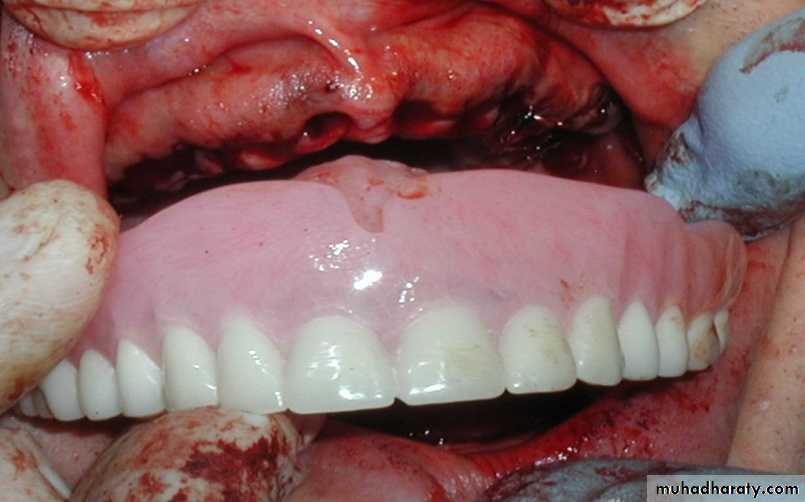

(5) Suturing of the sockets and insertion of the immediate denture.

Tooth set up and try in Extraction and insertion